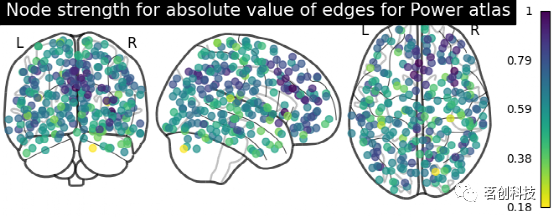

plot_markers:绘制网络节点。根据所提供的节点测量(即连接强度),自动绘制网络节点并对其进行颜色编码,如在不同参考图集上比较连接体。

# 计算每个节点的归一化绝对强度

node_strength = np.sum(np.abs(matrix), axis=0)

node_strength /= np.max(node_strength)

plotting.plot_markers(

node_strength,

coords,

title='Node strength for absolute value of edges for Power atlas',

)